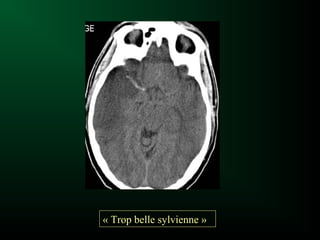

– ±Thrombus intra-artériel : Hyperdensité spontanée

de l ’artère cérébrale moyenne au stade aigu

« Trop belle sylvienne »